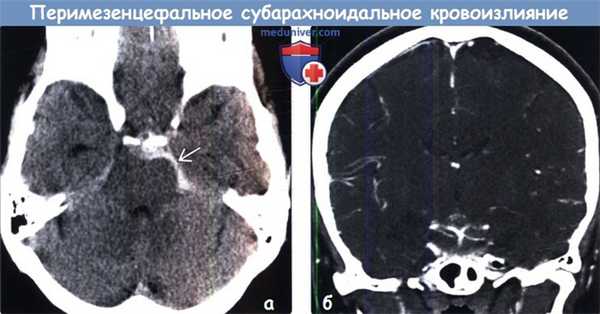

(б) Бесконтрастная КТ, аксиальный срез: у женщины 49 лет, поступившей в приемное отделение с «громоподобной» головной болью, определяется САК, локализующееся в перимезенцефальных цистернах и окружающее средний мозг. Обратите внимание на отсутствие крови в сильвиевой борозде и переднем супраселлярном субарахноидальном пространстве. (а) Бесконтрастная КГ, аксиальный срез: у этой же пациентки определяется скопление крови в субарахноидальном пространстве спереди от моста с распространением книзу.

(б) КТ-ангиография, корональный срез через бифуркацию основной артерии: у этой же пациентки признаков аневризмы не определяется. Гиперденсные сосуды легко различимы даже на фоне выраженного САК.

(б) Бесконтрастная КТ, аксиальный срез: у женщины 49 лет, поступившей в приемное отделение с «громоподобной» головной болью, определяется САК, локализующееся в перимезенцефальных цистернах и окружающее средний мозг. Обратите внимание на отсутствие крови в сильвиевой борозде и переднем супраселлярном субарахноидальном пространстве.4. Ангиография при перимезенцефальном субарахноидальном кровоизлиянии (пнСАК):

(а) Бесконтрастная КГ, аксиальный срез: у этой же пациентки определяется скопление крови в субарахноидальном пространстве спереди от моста с распространением книзу.